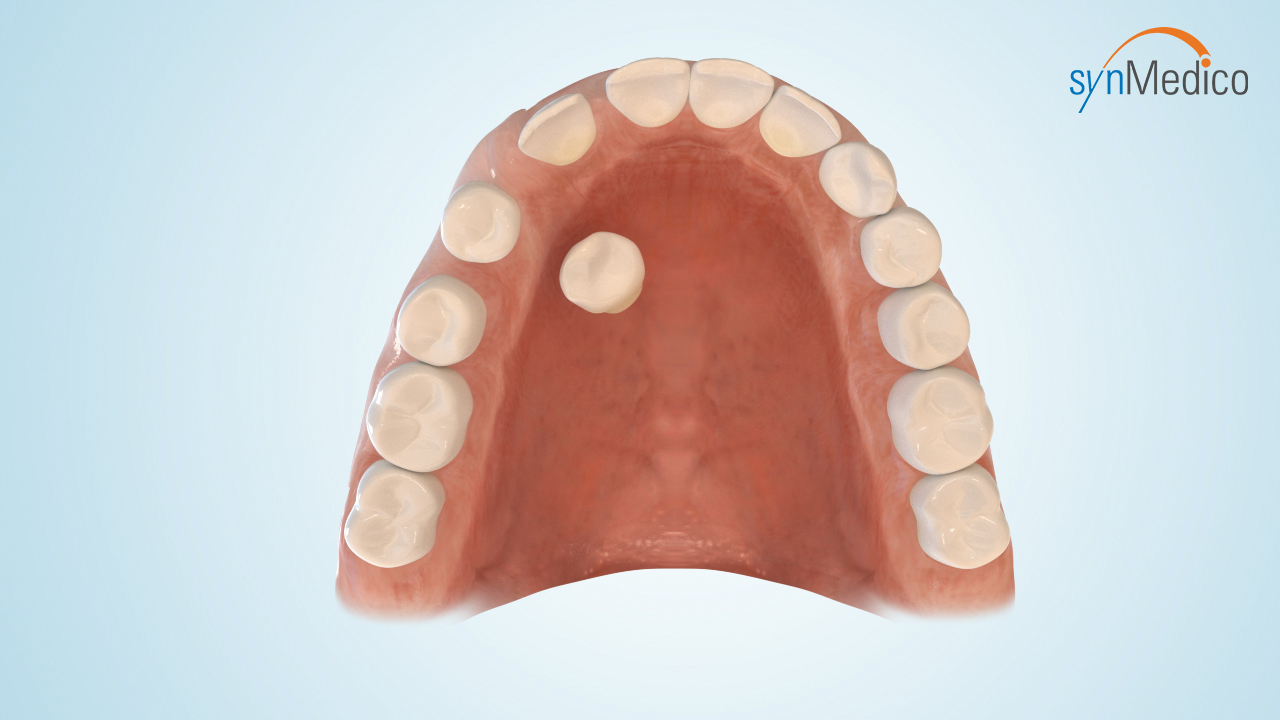

Freilegung von Zähnen

Gelegentlich verbleiben Zähne in der Wachstumsphase im Kiefer, da eine Blockade durch Nachbarzähne den Durchtritt verhindert. Durch eine kombinierte Behandlung mit den Techniken der Kieferorthopäde und der Kieferchirurgie können solche Zähne in die Zahnreihe eingestellt werden.